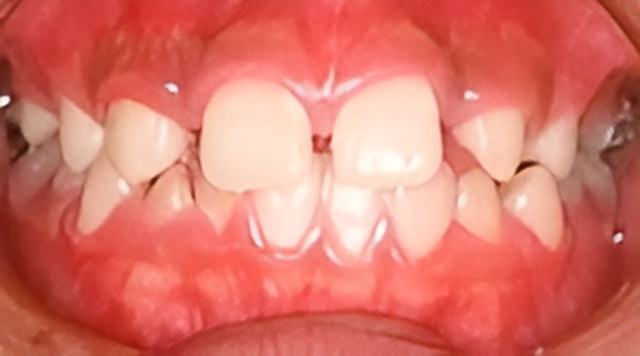

症例

歯列矯正 歯肉形態修正手術 インプラント メタルボンドを併用した症例です。

この治療では1本の歯も削ったり、抜いたりはしていません。

- 先天的に上顎側歯列が欠如している患者さんです。

- はじめに矯正治療を行い、本来歯があるべき位置に矯正して、インプラント手術のためのスペースを確保しました。

- 矯正治療終了後に歯肉の形態修正手術を行いました。

- 本来の側切歯部分にインプラント埋入

- メタルボンドにて修復